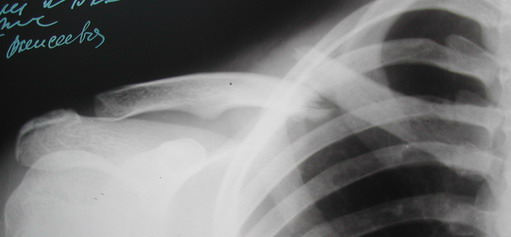

В приложении проект наших тезисов на съезд и клинический пример: Пациентка 23 лет поле неэффективного оперативного лечения (4 нед.) перелома ключицы спицей (была оперирована в С-Петербурге)(снимок после удаления спицы) и результат закрытого БИОС..